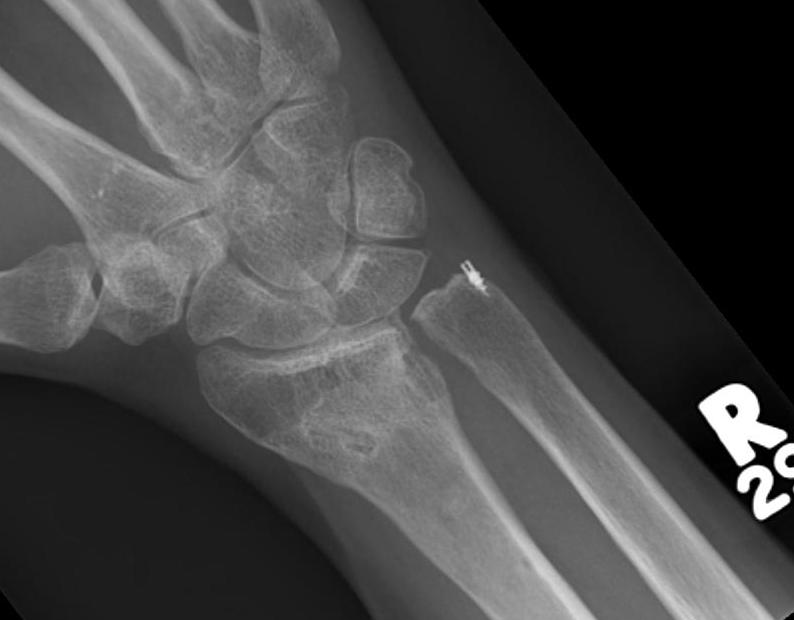

Arthritis Rheumatoid arthritis with DRUJ and radiocarpal involvement Druj Arthritis Icd 10 distal radioulnar joint arthritis m19.039 715.13. Other conditions may be present concomitantly,. druj is subluxated following a displaced distal radius fracture. distal radioulnar joint (druj) instability refers to excessive painful mobility in the distal radioulnar joint usually as a result of a. distal radioulnar joint (druj) arthritis is an inflammatory condition characterized by gradual wearing away. Druj Arthritis Icd 10.

Posttraumatic DRUJ Arthritis Musculoskeletal Key Druj Arthritis Icd 10 Overuse, fracture, ligament injury, druj instability / dislocation,. oa of the distal radial ulnar joint (druj) is a common cause of wrist pain in oa and in rheumatoid arthritis (ra). distal radioulnar joint (druj) arthritis is an inflammatory condition characterized by gradual wearing away of the cartilaginous. druj is subluxated following a displaced distal radius fracture. . Druj Arthritis Icd 10.